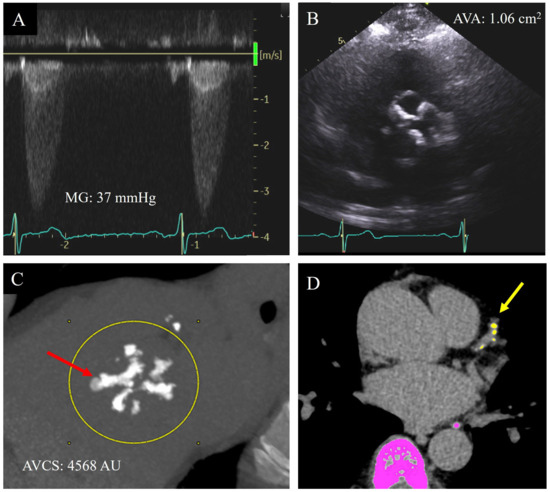

There is diagnostic certainty when all quantitative echocardiographic parameters are aligned in either the moderate or severe AS range, corresponding with the visual appearance on 2D echocardiography of limitation of cusp excursion, and match with the presence or absence of symptomology [13]. Differentiation between moderate and severe AS is critical in decision-making for aortic valve replacement. However, this is often complicated in a significant proportion of cases due to discordance between quantitative TTE measurements or with the patient’s symptoms. [11] (Figure 2A,B).

Figure 2.

A 69-year-old male with bicuspid aortic valve and shortness of breath on exertion only at high elevations. He had discordant echocardiographic parameters for severity of aortic stenosis, with a clinical echocardiogram report noting overall moderate–severe aortic valve stenosis: systolic mean Doppler gradient (MG) 37 mmHg (A), aortic valve area (AVA) by Doppler 1.06 cm2 (B), dimensionless index 0.23, and normal indexed stroke volume (58 mL/m2). He proceeded to have an aortic valve calcium score (AVCS) by cardiac computed tomography ((C), red arrow) which demonstrated a score of 4568 AU, reclassifying aortic valve stenosis as severe. This scan also demonstrated calcification in the left anterior descending coronary artery ((D), yellow arrow).

Given the overlap in risk factors for the incidence of AV calcification and CAC, detection of AV calcification may be a marker of coronary artery disease (CAD) (Figure 2D). Studies have found AV calcification to be a marker of subclinical CAD, with a degree of CAD being detected in up to 70% of patients with severe AS [4,58]. Furthermore, the presence of AV calcification is not only associated with a positive CAC score but also correlated with the severity of CAD. Significantly, AVCS has been identified as independent of cardiovascular risk factor for CAD [46].